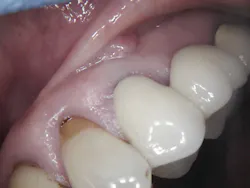

The patient, a 63-year-old female, presented for an emergency visit. She explained her situation, complaining of pain and a lump on the top-left quadrant of her mouth. After an oral evaluation and x-ray (figure 1), it was discovered that she had a large draining granuloma with swelling in the mucobuccal fold near teeth Nos. 12–14 due to a chronic periapical abscess (figure 2).